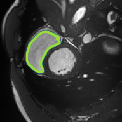

Despite their outstanding accuracy, semi-supervised segmentation methods based on deep neural networks can still yield predictions that are considered anatomically impossible by clinicians, for instance, containing holes or disconnected regions. To solve this problem, we present a Context-aware Virtual Adversarial Training (CaVAT) method for generating anatomically plausible segmentation. Unlike approaches focusing solely on accuracy, our method also considers complex topological constraints like connectivity which cannot be easily modeled in a differentiable loss function. We use adversarial training to generate examples violating the constraints, so the network can learn to avoid making such incorrect predictions on new examples, and employ the Reinforce algorithm to handle non-differentiable segmentation constraints. The proposed method offers a generic and efficient way to add any constraint on top of any segmentation network. Experiments on two clinically-relevant datasets show our method to produce segmentations that are both accurate and anatomically-plausible in terms of region connectivity.